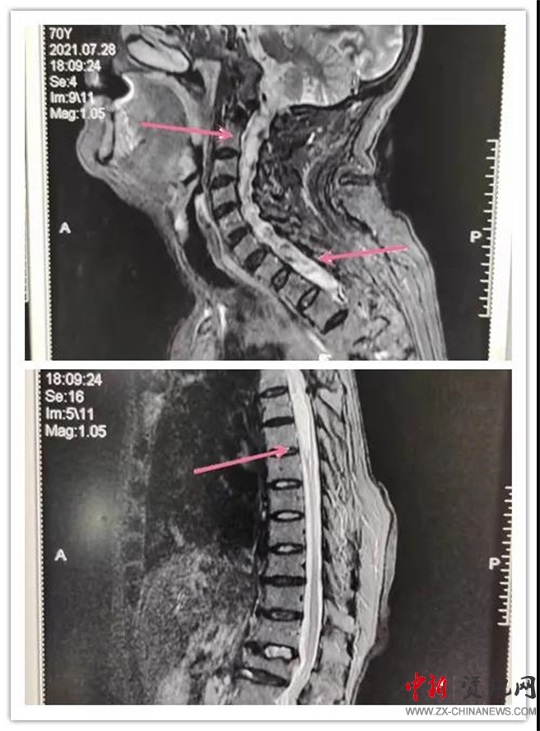

患者,女,70歲,六年前患脊髓空洞癥在某醫(yī)院行“脊髓空洞蛛網(wǎng)膜下腔分流手術(shù)”后病情好轉(zhuǎn)。近段時(shí)間,因“后肩部疼痛,無(wú)痛溫覺(jué)喪失,雙下肢疼痛、無(wú)力逐漸加重”癥狀加重,來(lái)汝南縣人民醫(yī)院就診,行MR檢查診斷為“頸胸脊髓空洞”。神經(jīng)外科副主任沈明輝認(rèn)真研究了患者的病情和 MR片子,認(rèn)為手術(shù)可行,隨即收住患者到科室;颊呷朐汉,完善了術(shù)前檢查,由于患者年事已高,患有高血壓、心臟病等疾病,使病情更加復(fù)雜,手術(shù)難度風(fēng)險(xiǎn)進(jìn)一步加大。手術(shù)團(tuán)隊(duì)組織了全科會(huì)診,對(duì)患者手術(shù)情怳進(jìn)行了分析。如果不做手術(shù),病情進(jìn)一步發(fā)展,患者雙下肢會(huì)截癱,再做手術(shù)也很難恢復(fù)。在得到患者家屬的理解和支持后,根據(jù)患者的病情,手術(shù)團(tuán)隊(duì)反復(fù)討論術(shù)中可能出現(xiàn)的問(wèn)題:完善圍手術(shù)期應(yīng)急預(yù)案,制定精準(zhǔn)的治療及手術(shù)方案,擇期為患者成功實(shí)施了“頸胸脊髓空洞胸腔引流”手術(shù)。術(shù)后患者雙下肢肌力明顯好轉(zhuǎn),正在康復(fù)中。

手術(shù)前